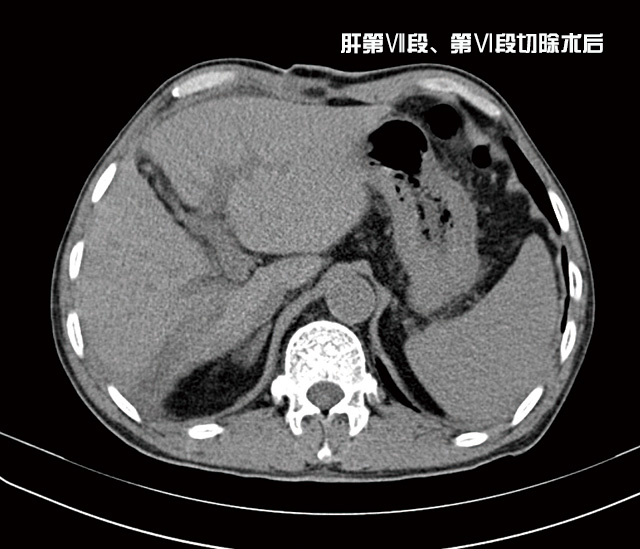

經(jīng)過充分準備后,由李森主任為他成功實施了肝第Ⅶ段、第Ⅵ段切除手術(shù),術(shù)后劉大爺恢復(fù)良好,精神抖擻,日前已康復(fù)出院。

據(jù)李森主任介紹,目前肝癌治療的首選方法是手術(shù)切除。如能早期發(fā)現(xiàn)并及時手術(shù),可提高遠期存活率和生活質(zhì)量,甚至達到根治的效果。但很多肝癌患者發(fā)現(xiàn)時,已是中晚期,因腫瘤巨大、伴肝硬化、肝功能差、肝內(nèi)轉(zhuǎn)移或多中心腫瘤存在等,而不能及時行手術(shù)治療,這種情況可以考慮先介入治療縮小癌瘤,待降期后再行手術(shù)切除,效果良好。目前肝巨大腫瘤的降期后手術(shù)切除為許多原來不宜手術(shù)切除的病人開辟了新路。